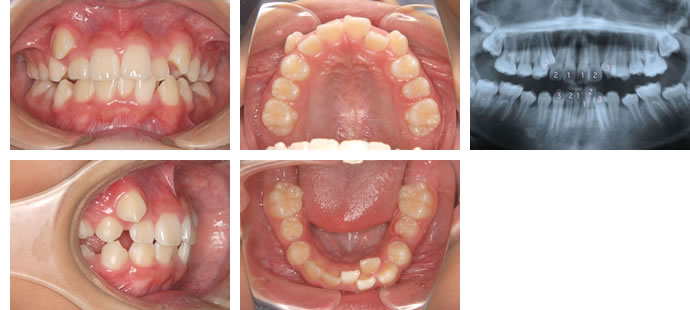

■治療開始時 10歳11ヶ月

4年の観察期間を経て、第一大臼歯までのすべての永久歯が生え揃いました。

初診時(6歳)と同じく下の前歯が重なっているだけでなく、十分なスペースを得ることができなかった上の犬歯(左右の3番)が横から萌出しており、重度の叢生症例となっています。あごを広げる床矯正を行っていたとしても、綺麗な歯列・正しい咬み合わせ・バランスが取れた口元を得ることはできなかったでしょう。

こちらの患者さんの場合は、永久歯が生え揃ったこの時期から治療を開始するのが最善と考えられます。